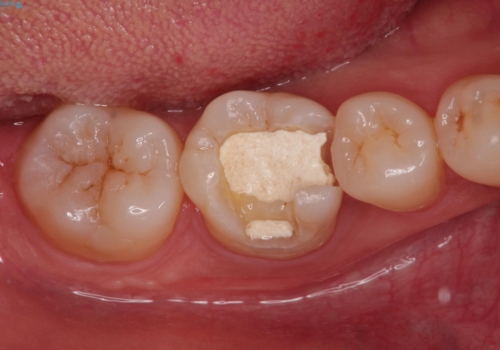

- 奥歯の治療の継続を主訴に来院された患者様です。

他院にて根管治療を行ったそうですが、ラバーダムを使用していなかったため、クラウン修復の前に当院の治療を希望され受診されました。

根管内に充填されている材料は、スカスカの状態で簡単に除去ができました。